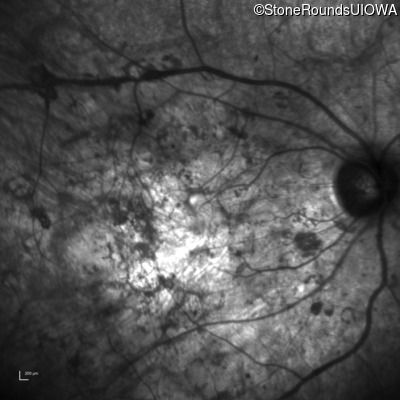

Age at visit: 33 years

OD OS